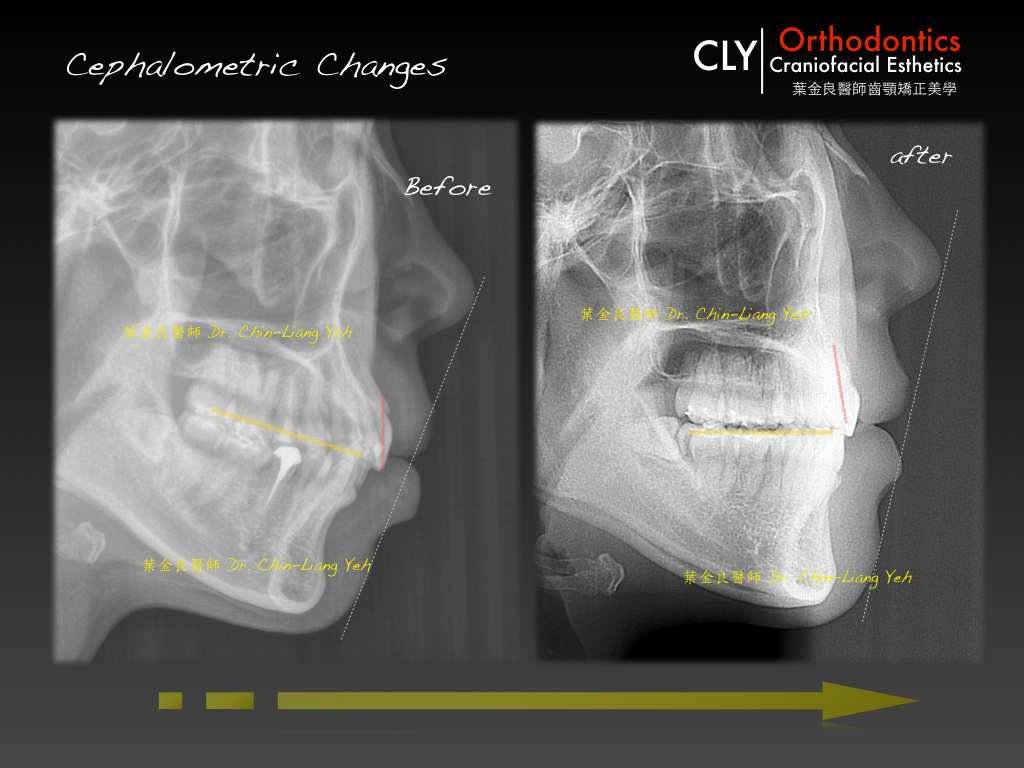

很特別地,齊杏矯正的病人大都是懂矯正的,都是為了更高層次的矯正治療而來,鮮少有只要求將齒列排整齊而已。原本已經整齊的齒列,很難說服其他人,自己需要矯正齒列的理由,然而當我們比對矯正前後的臉型與側顱 x ray ,即不難發現,原本過於前凸的直立上排前牙與過於明顯外暴的齒槽骨。

深咬泛指的是上排前方齒列覆蓋下排齒列有過多的現象,這也經常伴隨過多的牙齦外露問題。在本案例中,除了牙齦外露,並伴隨咬合平面過於傾斜,造成的下巴不足的現象。

我們從最重要的顏面曲線發想,最適當的齒列位置,是不能讓前牙露得太多,會失去質感。必須讓齒列適度後移,讓鼻唇的曲線更顯立體,經過我們拔除小臼齒,將前牙適度後移,並以大臼齒的移動引領下顎咬合平面的旋轉,讓下巴的位置更為前方,讓外觀上更為立體與美感。

我們不斷追逐矯正能帶來的顏面改變,就像鼻子與前牙之間的距離,因為適當的後移,讓臉型產生極大的影響,而這樣的移動絕非ㄧ般牙科治療所能比擬,感受齒列移動造成顏面的改變,是我們追逐的泉源,因為他能將平凡的東西化為神奇。